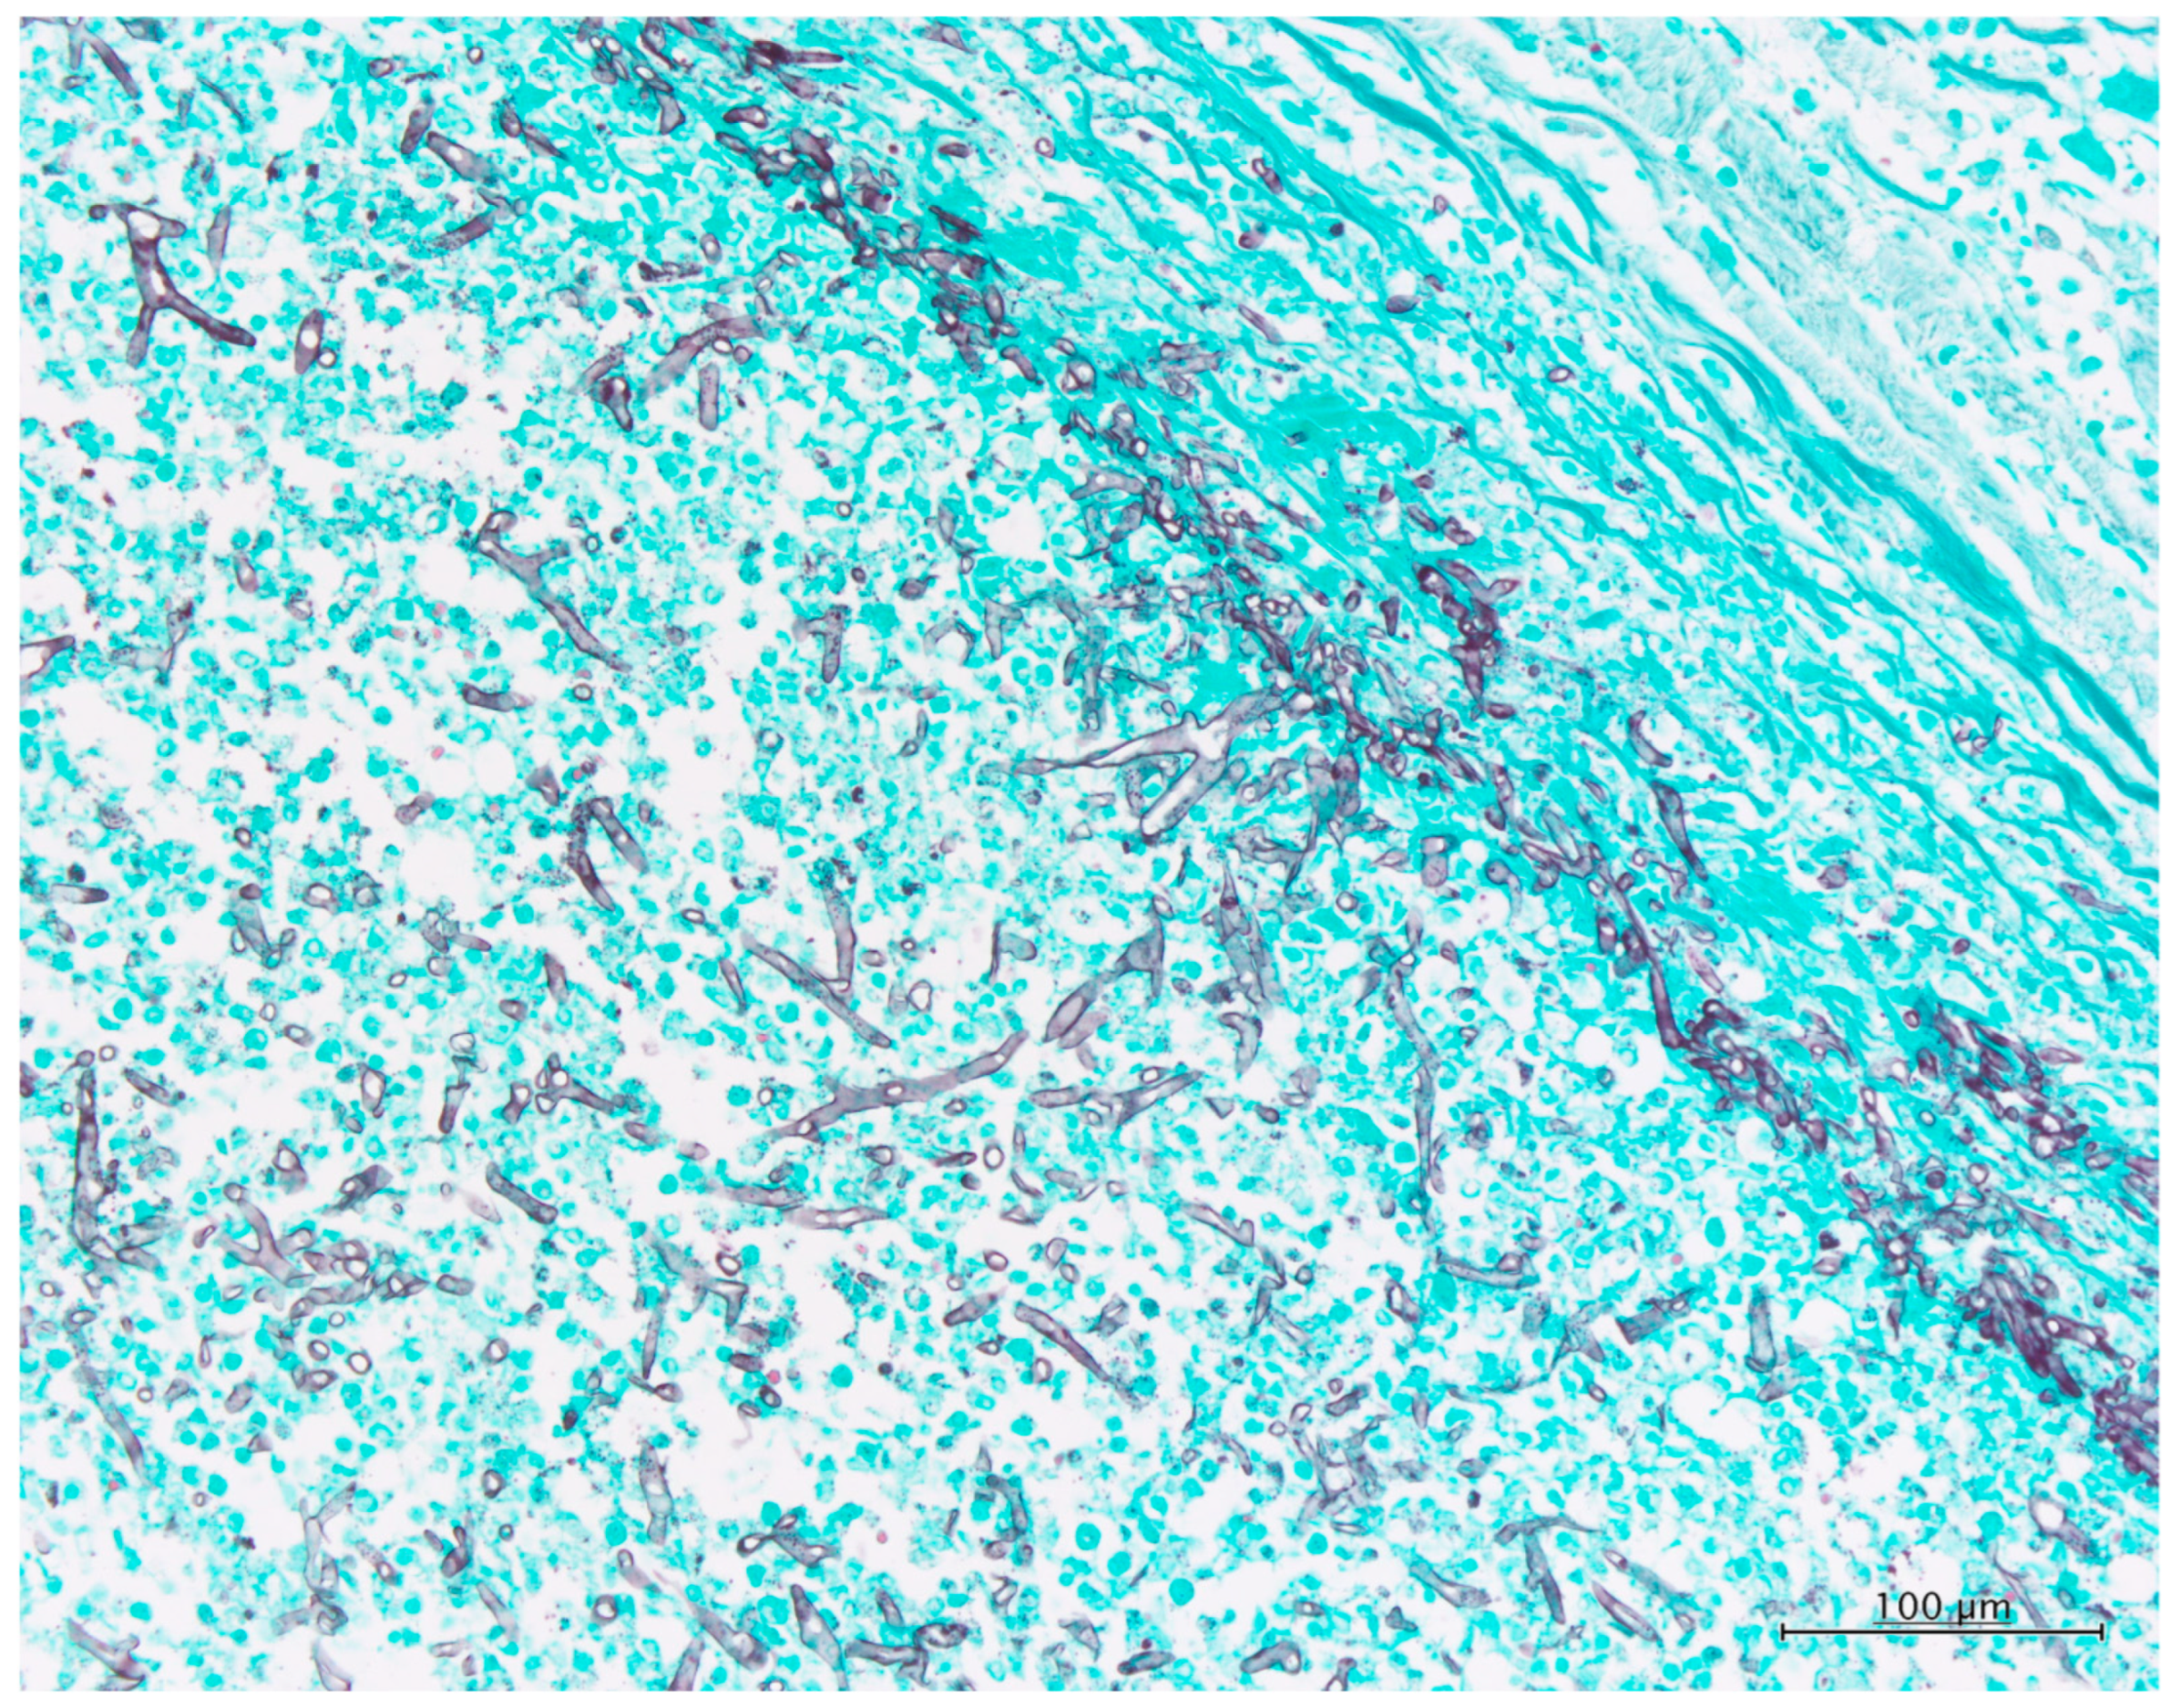

An autopsy excluding the brain was performed. The section of the myocardium revealed several foci of hemorrhagic necrosis measuring up to 15 mm in size at the posterior–lateral wall of the left ventricle. Furthermore, a verruca was found on the mitral valve. In addition to congestive edema in the lungs, a section of the upper lobe of the left lung revealed a hemorrhagic infarct measuring 80 × 60 mm2 in size. There were foci of necrosis in the spleen and three hemorrhagic ulcers of less than 100 mm in diameter on the large intestinal mucosa (Figure 1B–F). Histological examination revealed filamentous fungi in all of the aforementioned foci. The case was diagnosed as “mucormycosis” based on the typical hyphae morphology” (Figure 2 and Figure S7).

Figure 2. Histopathology findings of the autopsy case of the lung. Grocott’s stain (×200). Many hyphae in the lumen of the pulmonary artery have a thin and folded wall and show bifurcation with irregular angle, but rectangular bifurcation is occasionally noted. Septae are rarely found.